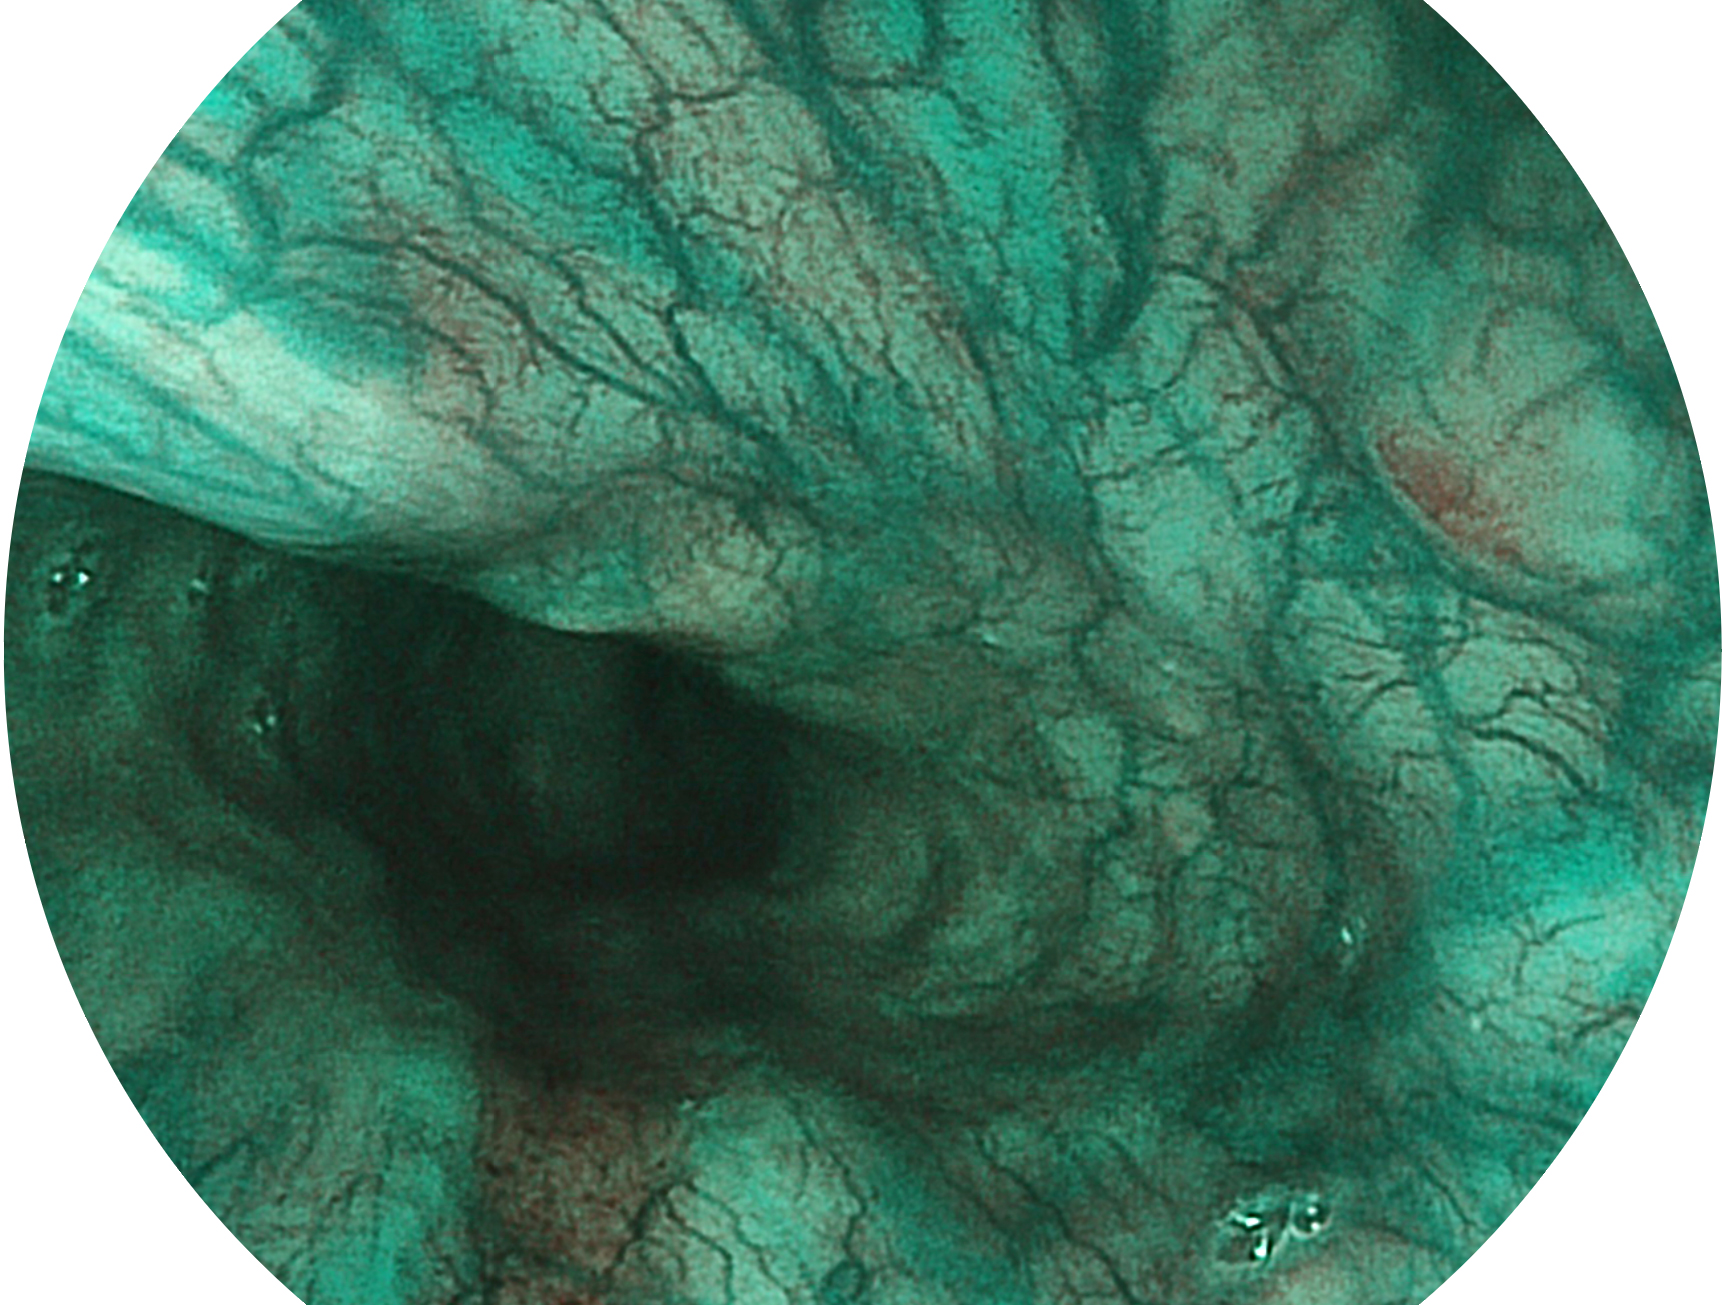

百老汇电子游戏官网新开发的内镜染色技术,主要是基于多波长LED 光源的开发,VLS-55Q 四波长LED 光源是由四个不同颜色的LED光按照相应照明模式所规定的特定发光比例进行合束后形成,合束后形成的照明光的光谱由红光、绿光、蓝光及蓝紫光这四个不同的波段范围构成。具有更高光谱自由度,通过光谱比例的控制,实现了聚谱成像技术,英文全称为“Spectral Focused Imaging, SFI”,缩写为“SFI”和光电复合染色成像技术,英文全称为“Versatile Intelligent Staining Technology, VIST”,缩写为“VIST”。